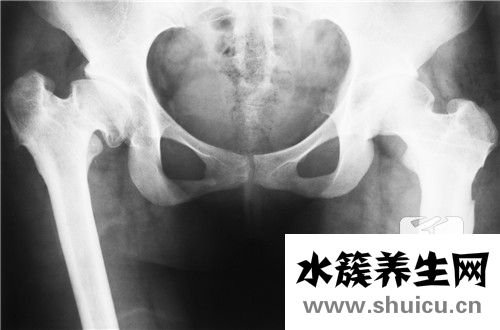

骨盆在醫(yī)學上被稱為板骨,因為骨盆看起來像一個盆,所以當嬰兒還在媽媽肚子里的時候,骨盆就是他們的窩床。所以在老一輩人的意識里,認為盆骨大的女人容易養(yǎng)是不無道理的。但是因為骨盆橫跨整個腰部,有些...